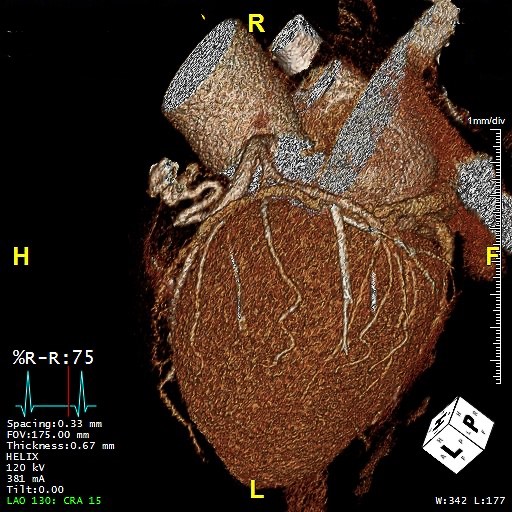

The authors present a 57-year-old woman with a left anterior descending to pulmonary artery fistula, causing progressive and daily ischemic chest pain associated with dyspnea and dizziness. Diagnosis was performed by coronary angiography and 3D computed tomography imaging reconstruction of the left anterior descending and pulmonary artery.

3D computed tomography imaging reconstruction of the LAD and PA and their insertion point to the PA are depicted.